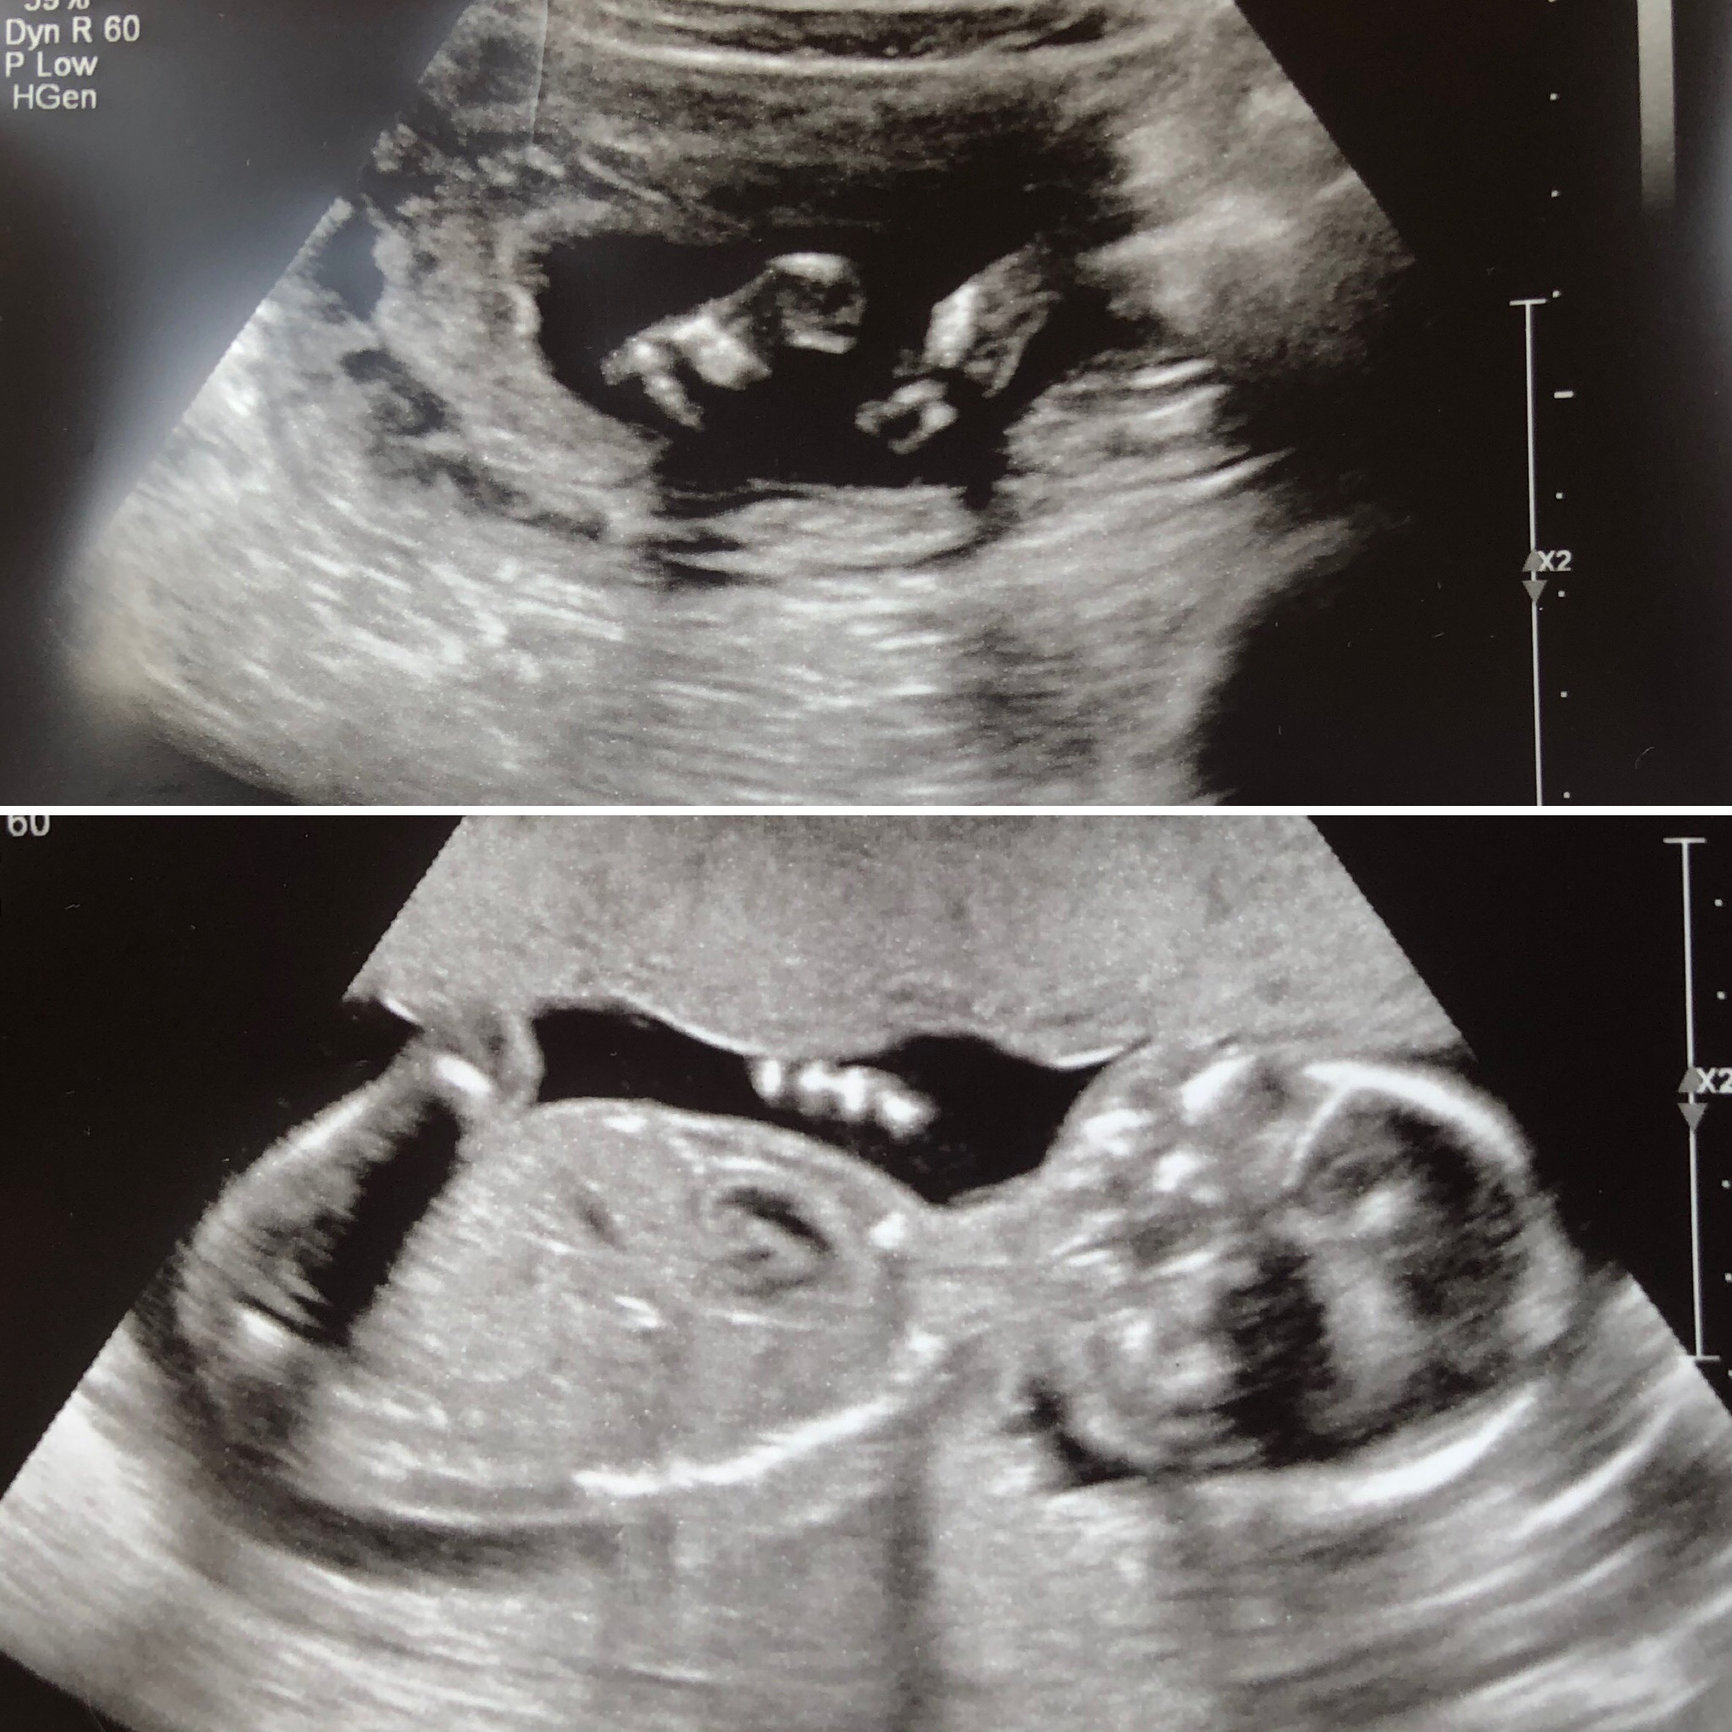

Just got my Gender Ultrasound done on Thursday at 16W 4 days. This is my final baby before tubal. After 2 boys and being told I'm having a girl I am beyond excited. The U/S lady told me she was pretty certain for a girl, she looked around for a.good 15 mins or so. She got the baby moving around a ton and managed to get these pictures. BUT I see this tiny little line between the legs on one of them and now I'm all conflicted.

@cpk3535 yeah yours definitely looks girl to me. That little tiny line between the legs in the one photo has me baffled though. And on all the other pictures there isn't the " 3 lines" like they say girls have. I will be getting another U/S done in about a month at 20 weeks. Hopefully she stays a girl!